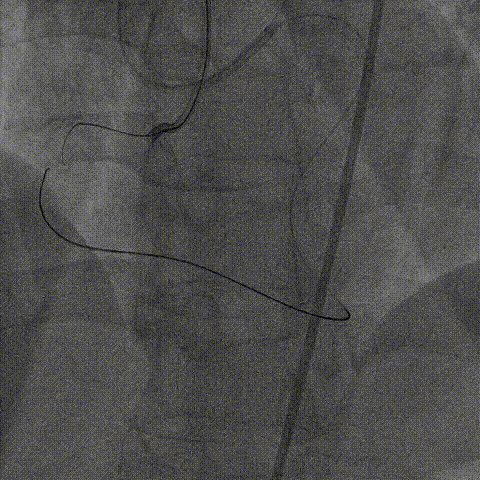

2、正向介入器械:Finecross微导管(130cm);XT-A导丝尝试寻找闭塞段入口及微通道,UB3尝试进入远段真腔失败,保留正向导丝启动逆向介入治疗。

右冠PCI

逆向器械:

1、选择近段粗大间隔支;Finecross(150cm);Sion导丝surfing通过侧枝循环至右冠远段,跟进微导管后尝试UB3、Gaia3导丝至闭塞段远段与正向导丝重叠,但闭塞段钙化可能导丝逆向导丝无法进一步前进突破。